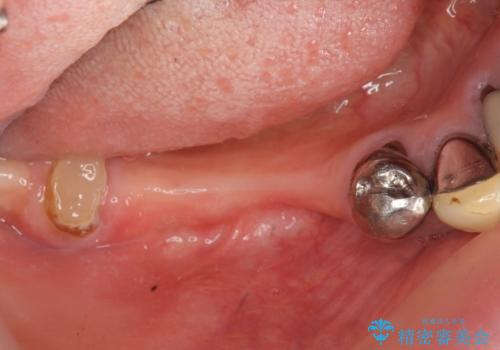

- インプラント治療を希望し数軒の医院で治療の相談をするも、骨の量が足りず治療が難しいと断られたのち当院にも相談にみえました。

長年の義歯の使用により骨の幅は非常に薄くインプラントを埋入するには大規模な骨の造成が必要な状態です。

また骨の問題だけでなく、完成後に歯ブラシがしやすいよう歯ぐきの移植も行いよりインプラント周囲の環境が安定するよう環境を整える治療計画を立てます。